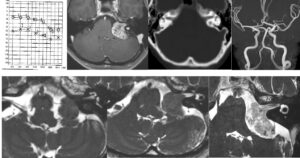

左海綿静脈洞内髄膜腫(複視)に対して、現在のスタンダードは放射線治療になりつつありますが、これも長期制御が困難なので、今回はBTOで左内頸動脈閉塞による血管内腫瘍塞栓を行う計画としました。それに先立ち、BTO時のStump <50mHgであったためSTA-MCAバイパスを行いました。